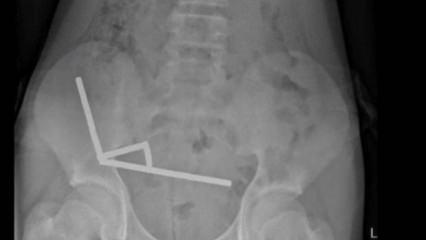

GÜNCEL4 YIL ÖNCEKüçük Uras'ın karın ağrısının nedeni herkesi şaşırttı! Bağırsağından 19 tane çıktıİstanbul'da yaşayan 4.5 yaşındaki Uras Aslan Aktaş, şiddetli karın ağrısı şikayetiyle ailesi tarafından hastaneye götürüldü. Çekilen röntgen filmi sonucu küçük çocuğun bağırsağında tam 19 tane 'neodyum mıknatıs' tespit edildi. Çocuk Cerrahisi Uzmanı Prof. Dr. Ali Çay tarafından ameliyata alınan Aktaş, sağlığına kavuştu. -